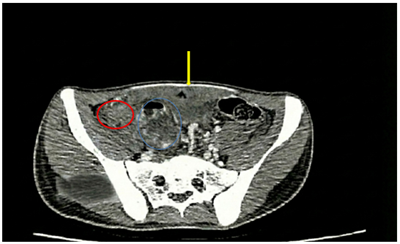

ĐIỀU TRỊ UNG THƯ ĐẠI TRÀNG BỊ VỠ U TRÊN BỆNH NHÂN VỊ THÀNH NIÊN Ngày đăng: 29/01/2026 Ung thư đại trực tràng là một trong những bệnh lý ác tính phổ biến nhất trên toàn cầu cũng như tại Việt Nam. Theo GLOBOCAN 2022, bệnh đứng hàng thứ 4 về tỷ lệ mắc mới và thứ 5 về tỷ lệ tử vong [1]....